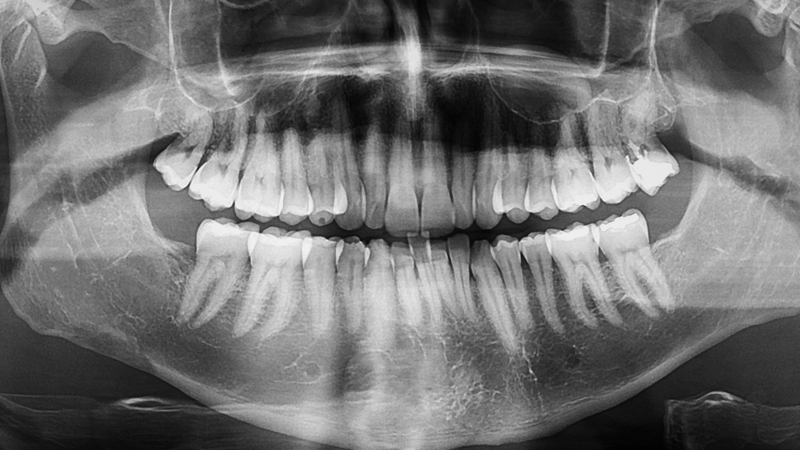

Việc điều trị răng móm tùy thuộc vào nguyên nhân (do răng hay do xương) và mức độ lệch khớp cắn. Bác sĩ sẽ thăm khám, chụp phim để xác định hướng điều trị phù hợp.